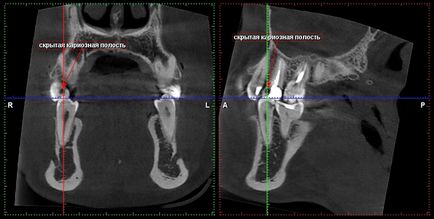

Terápia: jelenléte rejtett üregek

fogszuvasodás és a foggyökér